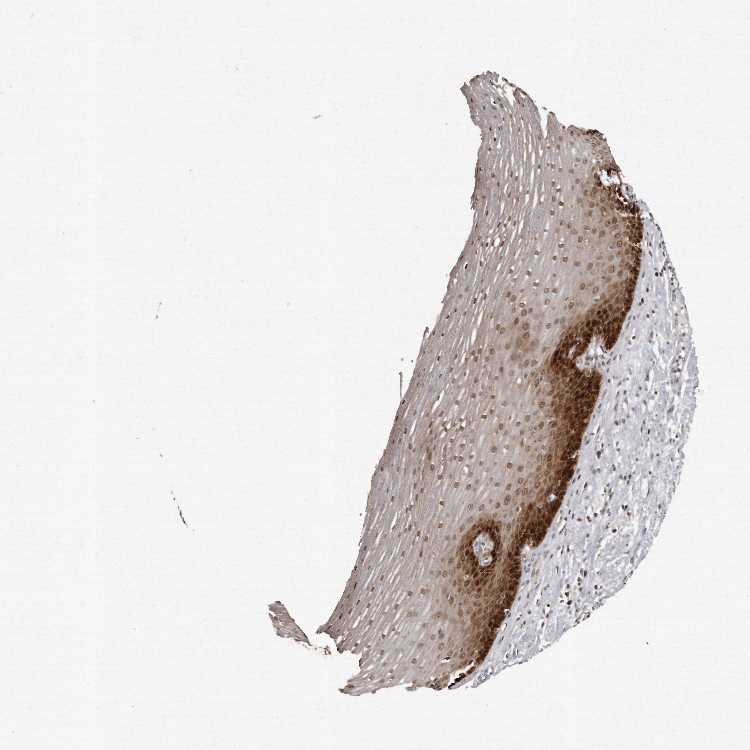

ESOPHAGUS - Antibody stainingi

Antibody staining in the annotated cell types in the current human tissue is reported as not detected, low, medium, or high, based on conventional immunohistochemistry profiling in selected tissues. This score is based on the combination of the staining intensity and fraction of stained cells.

Each image is clickable and will lead to virtual microscopy that enables deeper exploration of all samples and also displays staining intensity scores, fraction scores and subcellular localization as well as patient and tissue information for each sample.

Antibody HPA028612

Squamous epithelial cells High